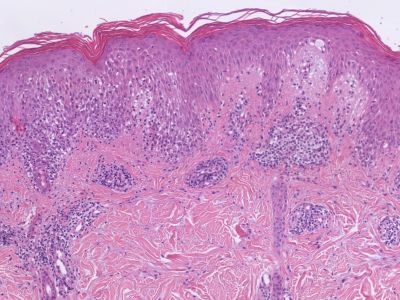

PA:Het klinisch beeld is wisselend, de PA ook.

In de beginfase enige spongiose en acanthose in de epidermis; in de cutis aanvankelijk uitsluitend wijde bloedvaten, vooral oppervlakkig. Perivasculair oedeem en infiltraatmantels, in intensiteit variërend van licht tot matig, vaak gemengd met polynucleaire leukocyten en eosinofielen. Het endotheel is wat gezwollen, de vaatwand verdikt.

Bij verdere ontwikkeling neemt de spongiose in de epidermis toe, de epidermis laat pleksgewijs los van de cutis; de subepidermale holten conflueren later tot bullae. In een nog latere fase ontstaat soms partiële necrose, van onder af, onder het blaardak. In de cutis bevinden zich dichte perivasculaire lymfocytaire infiltraatmantels, vooral onder de bullae; gewoonlijk bevinden zich hier slechts enkele eosinofielen, maar het kunnen er wel eens zeer vele zijn. De lymfocyten dringen het stratum papillare en de epidermis in; dit gaat gepaard met een sterke mate van oedeemvorming.

![Histologie erythema multiforme (click on photo to enlarge) [source: Kevin Kwee / Afdeling Pathologie MUMC] Histologie erythema multiforme](../../../pacoupes/thumbnails/erythema-multiforme.jpg) |

ingescande coupe (zoom) |

Bron

hoge resolutie PA-foto: Kevin Kwee en Afdeling Pathologie MUMC. Klik

op de afbeelding om in te zoomen.